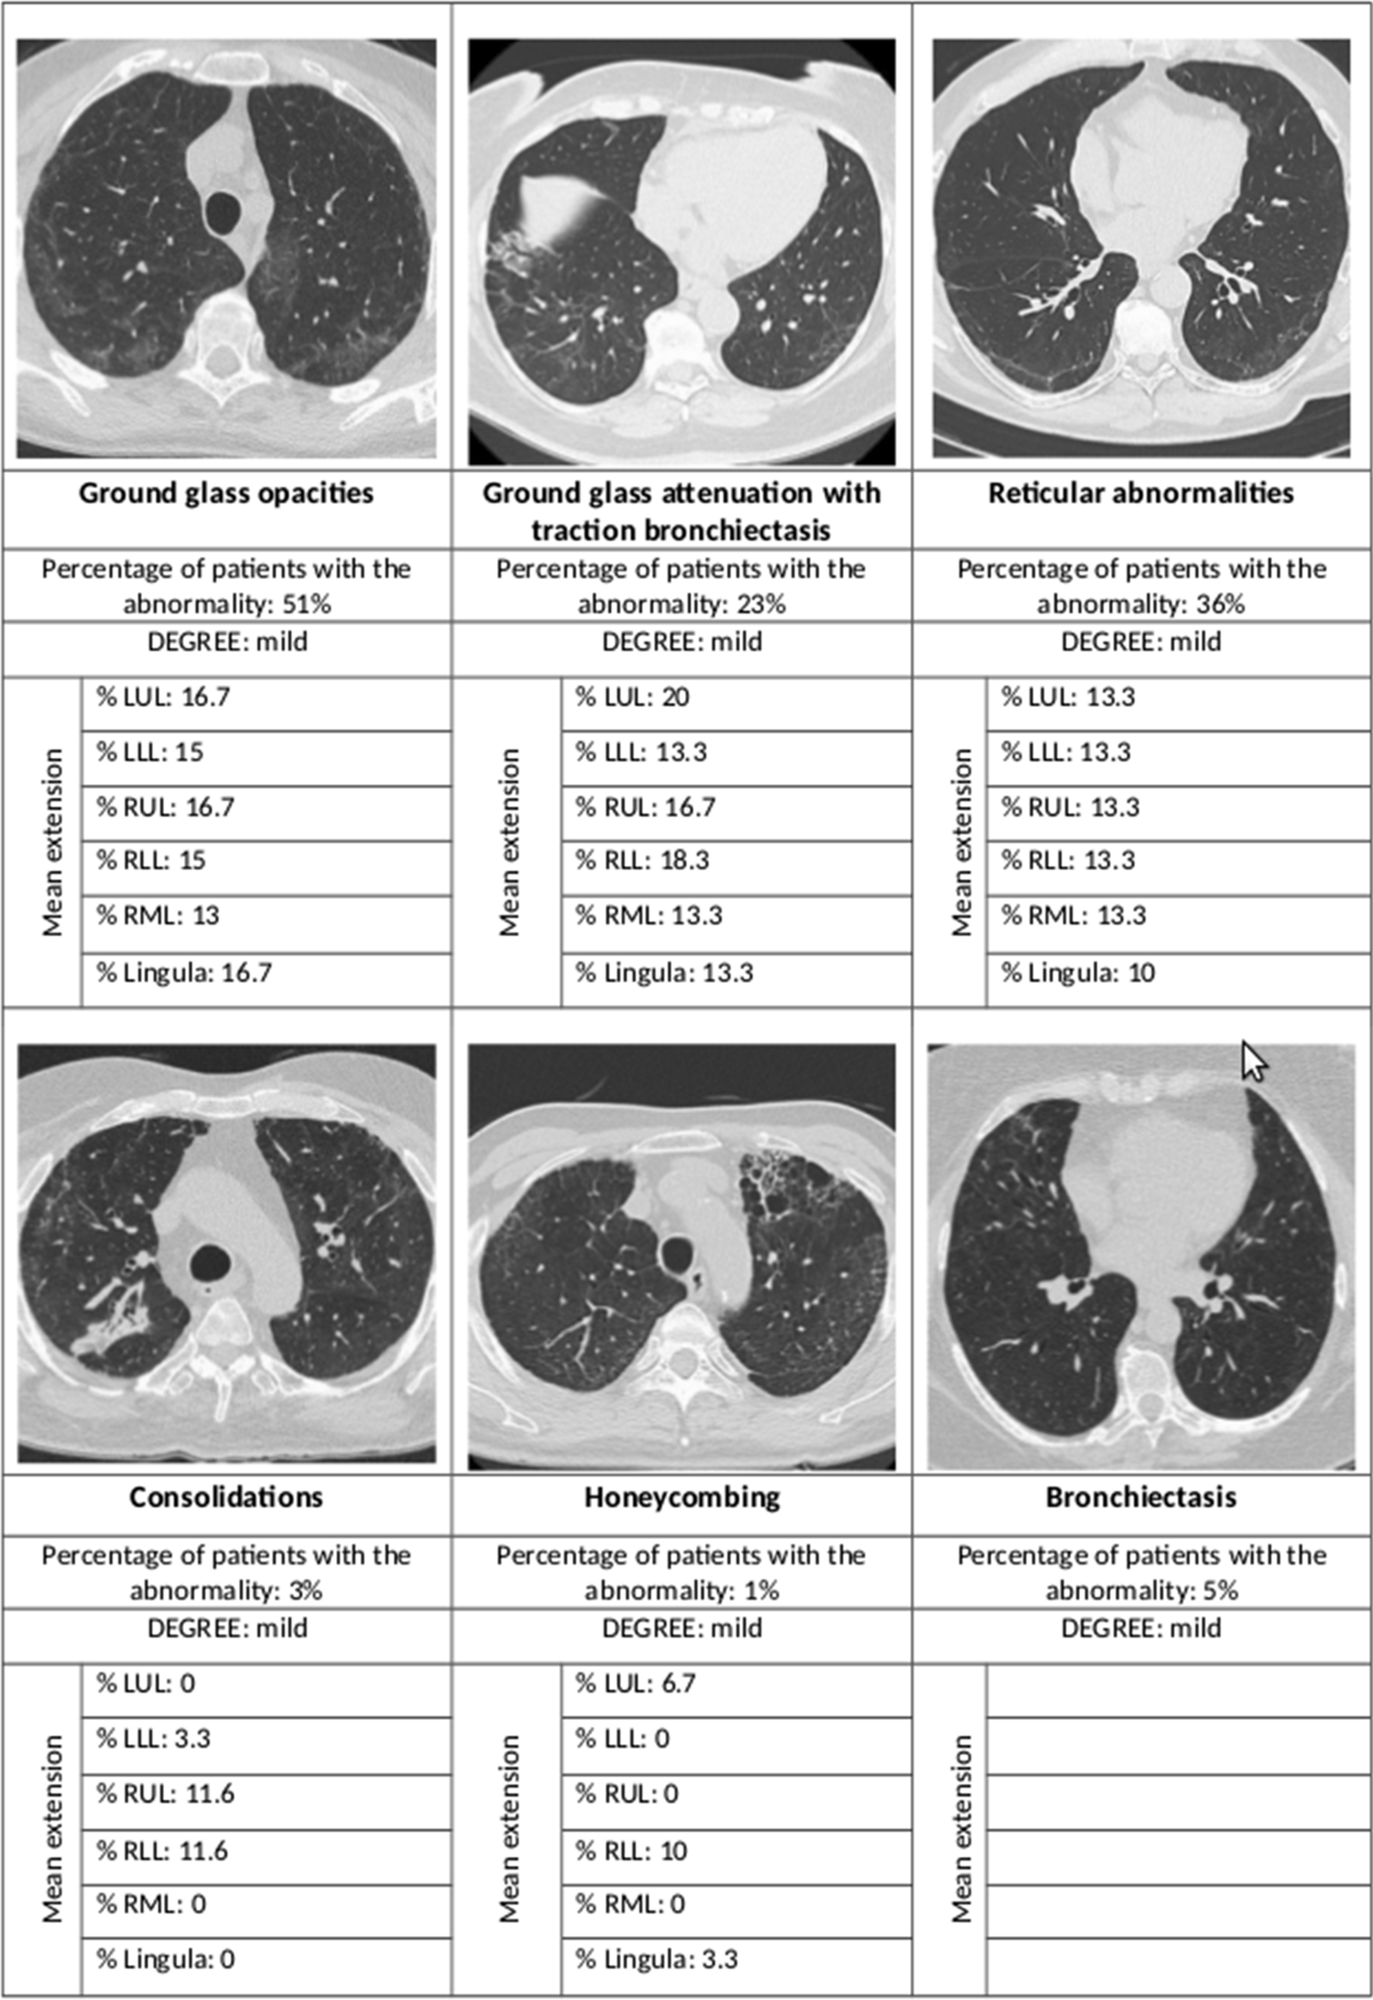

Summary of the main radiological abnormalities and their extension according to the lung lobe involved. LUL left upper lobe, LLL left lower lobe, RUL right upper lobe, RLL right lower lobe, RML right middle lobe

Most of the high-resolution CT (HRCT) scans showed interstitial lung changes; over half showed ground-glass opacities, over a third had reticular abnormalities, while less than 5% each showed consolidations and honeycombing. In 44% the ground glass opacities were accompanied by traction bronchiectasis or bronchiectasis.

Among patients with a normal DLCO, almost 60% had HRCT abnormalities, but when the DLCO was impaired, the proportion of radiological abnormalities went up to 77%. The same applied to ground-glass opacities, at 45% and 61%, respectively. Reticular abnormalities occurred in 28% and almost 50%, respectively.